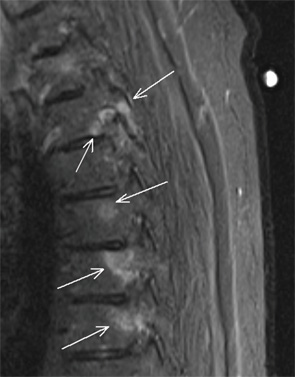

Findings/Diagnosis

A posteroanterior supine radiograph of the sacroiliac (SI) joints (see Figure 1) demonstrates bilateral symmetric erosions of the SI joints without ankylosis and mild reactive sclerosis of both iliac bones adjacent to the joints (black circles). Review of thoracic and lumbar spine MRI examinations obtained two years prior to presentation show scattered areas of vertebral body bone marrow edema, centered at the vertebral body endplates and pedicles in the thoracic spine (see Figure 2, arrows) and in the anteroinferior corner of the L5 vertebral body in the lumbar spine (see Figure 3, arrow). Although initially interpreted as nonspecific, the MRI findings are consistent with spondylitis.

Based on the previous MRI findings of spondylitis and the current radiographic presence of symmetric erosive sacroiliitis, a diagnosis of ankylosing spondylitis was made. Subsequent HLA-B27 testing was positive, and the patient was started on therapy.

Figure 2